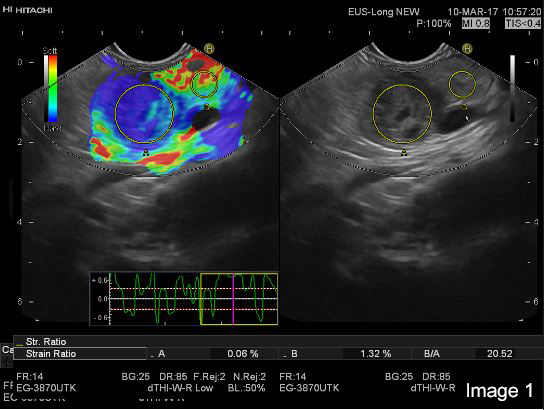

On colour-Doppler a “basket sign” was visible with several vessels highlighting the immediate surrounding tissue (Image 3).

After the intravenous administration of 1.7 ml (full vial) of Sonazoid® in a cubital vein, the tumour tissue was visualized as isoechoic compared to surrounding parenchymal pancreatic tissue. The cystic areas within the cystic tumour was shown with clear demarcation to the hypoechoic tumour tissue and were larger than expected by the B-mode image. In the late (venous) phase, particularly visible after 1 min and 20 seconds, the tumour tissue washes out contrast compared to the surrounding pancreatic parenchyma (Image 3).

Image 3:The hypoechoic tumor tissue in the B mode image is repeatedly corresponding to the blue area indicating harder tissue in the elastogram (left)